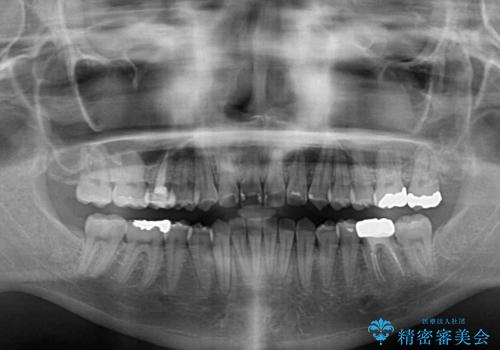

前歯のクロスバイト ギラギラのワイヤー装置で矯正治療

- 矯正装置

- メタルブラケット

- 前歯のクロスバイトを改善したいとのことで来院された患者様です。

マウスピース矯正では前歯の神経への負担が大きいことを懸念され、ワイヤー装置による矯正治療を行うこととしました。

クロスバイトが改善する際は、前歯しか接触しないため、痛みがあったり食事が取りにくかったりと、不便な時期がありますが、1年強の短期間で無事に治療を終えることができました。